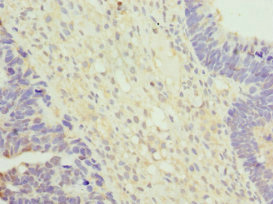

Immunohistochemistry of paraffin-embedded human ovarian cancer using CSB-PA839401ESR2HU at dilution of 1:100

Immunohistochemistry of paraffin-embedded human testis tissue using CSB-PA839401ESR2HU at dilution of 1:100